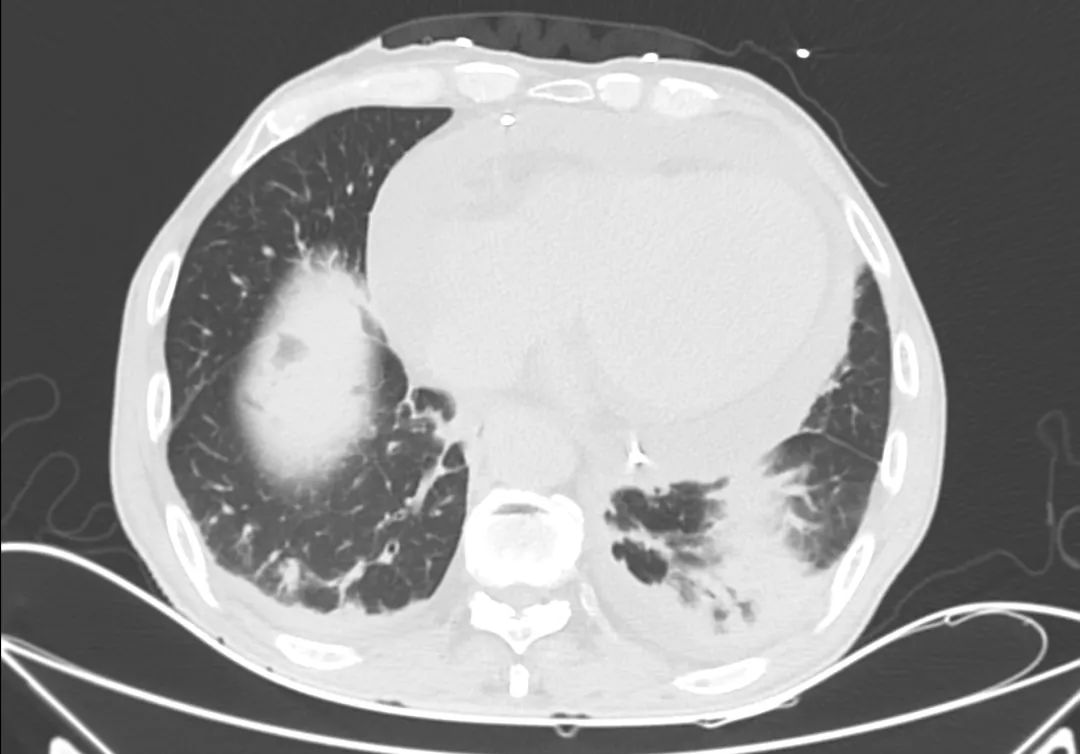

胸部CT